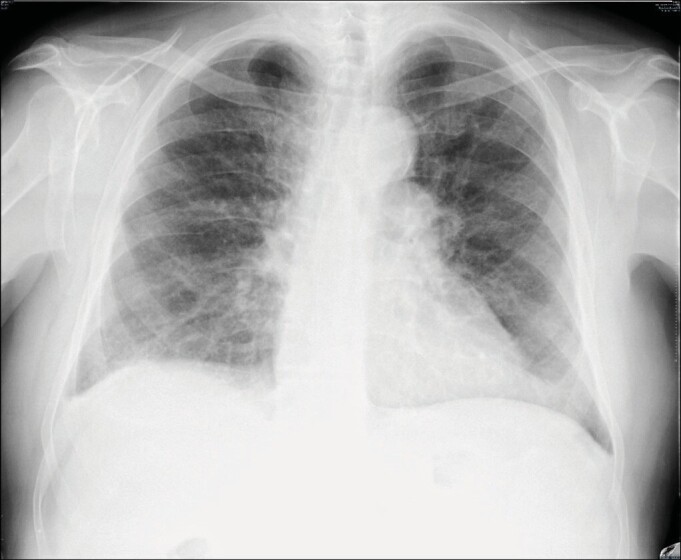

It is important to make the differential diagnosis of restrictive changes associated with hepatic hydrothorax or hepatopulmonary syndrome seen in the later stages of chronic liver diseases and restrictive changes associated with interstitial lung disease. Lymphocytic interstitial pneumonia (LIP) is in the rare idiopathic interstitial pneumonia subgroup of interstitial lung diseases. LIP is a rare disease, and its incidence is unknown. LIP is characterized by infiltration of the alveolar interstitium with lymphocytes, plasma cells, and histiocytes. The etiology of LIP includes idiopathic causes, rheumatological diseases, immune deficiencies, viral infections, and drug-related causes. Chronic liver diseases are also rarely included in the etiology of LIP. A 75-year-old male patient who was followed up for liver cirrhosis presented with dyspnea. He had hypoxemia in the arterial blood gas. In the thorax and abdominal computed tomography, irregular reticulations in bilateral lungs, ground-glass opacities, and scattered air cysts in both lung parenchyma, chronic liver parenchymal disease, splenomegaly, chronic portal vein thrombosis were determined. Clinical and radiological changes in the patient were evaluated in favor of interstitial lung disease. Although histopathological diagnosis could not be made, the patient whose radiological pattern was compatible with LIP was evaluated together with clinical findings and was accepted as lymphocytic interstitial pneumonia. He was evaluated in terms of diseases that could cause LIP. He was accepted as LIP due to chronic liver disease. Although histopathological examination is the gold standard for the diagnosis, a biopsy could not be performed in our case. Radiological and clinical findings were considered sufficient for the diagnosis of LIP. Chronic viral hepatitis and cirrhosis are also present in the etiology of LIP. Our case is presented as an example in the literature because it is a case of LIP due to chronic liver disease, and it is rare.